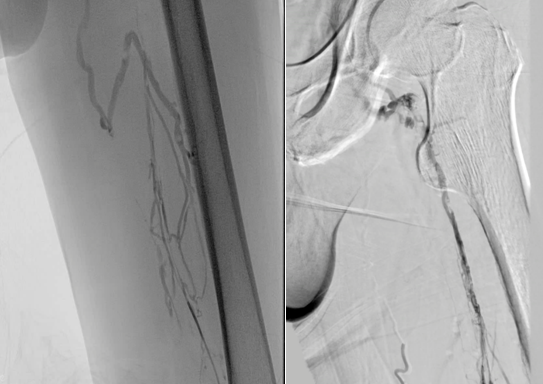

彩超引导下穿刺左侧腘静脉行造影示:左侧髂股静脉管腔闭塞,大量侧支循环建立。

利用超滑导丝及微导丝反复尝试通过髂股静脉闭塞段引入球囊扩张导管行髂股静脉球囊扩张成形,扩张过程中可见明显切迹。